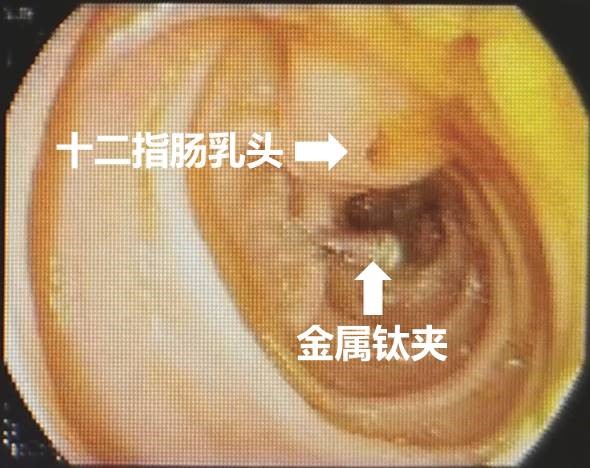

面对如此紧急的情况,干部保健病区冯建军主任联合消化内科赵刚副主任迅速启动了绿色通道,为刘爷爷进行了初步的稳定治疗,同时召集多学科专家进行紧急会诊。专家们一致决定先进行胃镜检查,了解患者既往手术方式,同时为可能的ERCP操作进行“探路”。后经胃镜检查,明确老人确实为“毕Ⅱ式远端胃部分切除”术后改变,内镜下反复寻找后,终于找到输入袢肠管以及十二指肠主乳头,同时为了后续手术时便于再次寻找,以一枚金属夹在十二指肠主乳头旁侧进行标记。

赵刚副主任凭借丰富的经验和精湛的技术,运用胃镜佩戴透明帽顺利找到前期设定的钛夹标记及十二指肠主乳头,然后利用专业器械,在内镜精细操作下,成功进行乳头括约肌切开及球囊扩张术,并最终将胆管内结石顺利取出。整个操作用时不到20分钟。

毕Ⅱ式胃大部切除术后的ERCP操作难度比普通ERCP超出很多,首先就是内镜的选择,按照《中国ERCP指南(2018版)》的建议,推荐首选十二指肠镜进行操作,但十二指肠镜在进镜操作以及寻找输入袢和十二指肠乳头方面明显不如直视镜。消化内科团队通过前期数年来的工作积累,制定了毕Ⅱ式胃大部切除术后ERCP操作的“交大二附院流程”,那就是先进行胃镜检查,由操作者亲自确认术式、输入袢肠管的走行以及十二指肠主乳头的位置,同时在内镜下对乳头进行定位标记,另外,对于输入袢开口较为隐蔽或内镜通过输入袢口较为困难的病例,操作者也会在输入袢口处额外进行标记,以便于后续ERCP操作时的二次寻找。在手术操作过程中,消化内科ERCP团队一般都会选用胃镜佩戴透明帽进行操作,透明帽一方面有利于进镜寻找目标肠袢,另一方面也可提高乳头插管时的镜身稳定性。